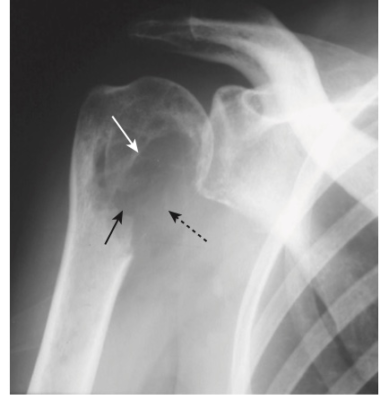

- Tiêu xương dưới màng xương, đặc biệt là ở mặt quay của đốt giữa của ngón trỏ và ngón giữa (Hình -2)

- Ăn mòn đầu xa xương đòn (Hình -3)